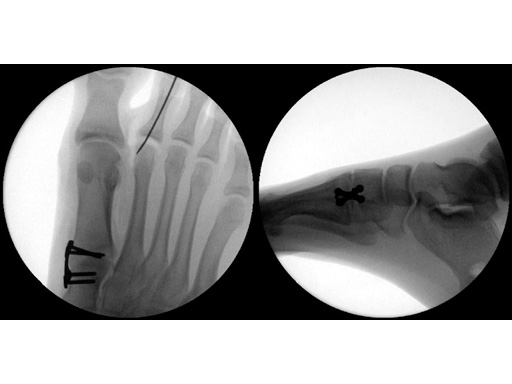

Case 2: 16-year-old male

Proximal first metatarsal growth-plate injury resulting in haluxvalgus. Arthrosis of first tarsometatarsal and second metatarsal hammer toe. Pain during activities and in general shoe wear.

Case provided by Carl Hasselman, Pennsylvania, USA

First MTP fusion and modified McBride with a distal softtissue release and second metatarsophalangeal (MTP) capsulotomy. A mini tight rope was used to hold and reduce the alignment of the first metatarsal. The X-plate was used to hold rigid fixation of the fusion. A K-wire was used for the second MTP capsulotomy.